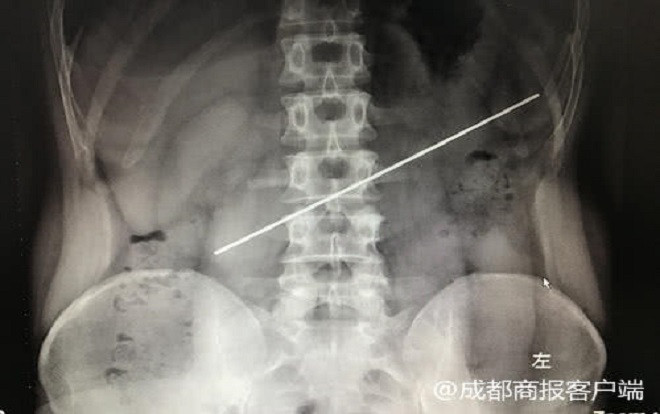

Thanh thép dài 20 cm nằm ngang dạ dày bệnh nhân. Ảnh: 成都商报客户端

Qua hình ảnh X-quang, các bác sĩ phát hiện thanh thép nằm ngang dạ dày và mắc kẹt trong đó, một phần đâm vào khoang bụng. Bác sĩ Lưu, phó giám đốc bệnh viện cho hay: “Trong 16 năm làm nghề y, đây là di vật dài nhất tôi lấy ra từ bụng bệnh nhân”.